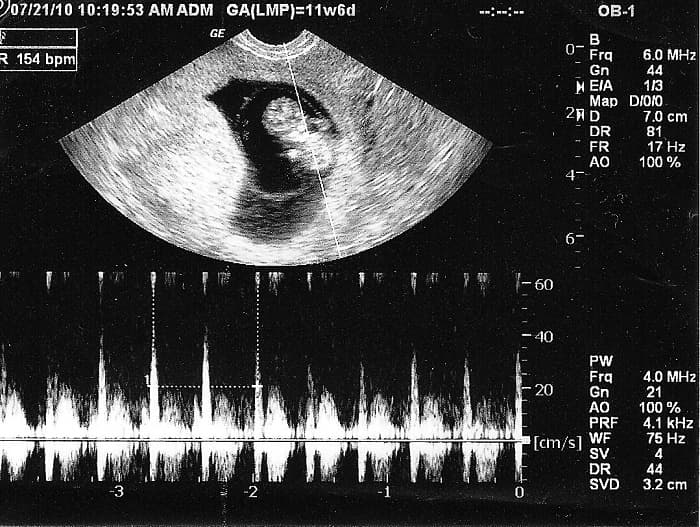

Ở giai đoạn đầu thai kỳ khi đi siêu âm, mẹ có thể nhận được kết quả tim thai dương tính (tim thai +) mà chưa ghi rõ nhịp tim. Điều này có nghĩa là đã có tim thai nhưng do thai nhi còn quá nhỏ nên chưa có nhiều thông số khi siêu âm. Mẹ hãy chờ thêm khoảng 1-2 tuần nữa khi siêu âm lại thì sẽ có được kết quả cụ thể hơn. Nhịp tim thai 7 tuần là bao nhiêu

Thông thường, tim thai đập khoảng 120-170 nhịp/phút, có lúc lên 180 nhịp/phút nếu bé cựa quậy. Có nhiều người quan niệm rằng tim thai bé trai sẽ đập chậm hơn tim thai bé gái. Tuy nhiên điều này không được khoa học ủng hộ. Nhiều nghiên cứu chỉ ra là nhịp tim thai và giới tính của bé không liên quan đến nhau.

3. Nhịp tim thai bình thường

Nhịp tim thai biểu hiện cho sức khỏe của thai nhi. Tim thai quá chậm hoặc quá nhanh đều cần phải thận trọng.

Thông thường, nhịp tim thai yếu sẽ nguy hiểm hơn nhịp tim nhanh. Ở giai đoạn tuần 6-8 nếu nhịp tim thai dưới 70 nhịp/phút thì nguy cơ sảy thai sẽ rất cao, khoảng 90%, dưới 90 nhịp/phút là 86% và dưới 120 nhịp/phút là 50%.

Nếu nhịp tim nhanh trên 160 nhịp/phút hoặc dưới 120 nhịp/phút thì có thể thai nhi đang bị thiếu oxy. Khi gặp những bất thường về tim thai, mẹ cần nhanh chóng đến gặp bác sĩ để được thăm khám và điều trị kịp thời.